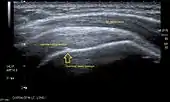

Ultrasound

There are several advantages of ultrasound. It is relatively cheap, does not emit any radiation, is accessible, is capable of visualizing tissue function in real time, and allows the performance of provocative maneuvers in order to replicate the patient’s pain.[26] Those benefits have helped ultrasound become a common initial choice for assessing tendons and soft tissues. Limitations include, for example, the high degree of operator dependence and the inability to define pathologies in bones. One also has to have an extensive anatomical knowledge of the examined region and keep an open mind to normal variations and artifacts created during the scan.[27]

Although musculoskeletal ultrasound training, like medical training in general, is a lifelong process, Kissin et al. suggests that rheumatologists who taught themselves how to manipulate ultrasound can use it just as well as international musculo-skeletal ultrasound experts to diagnose common rheumatic conditions.[28]

After the introduction of high-frequency transducers in the mid-1980s, ultrasound has become a conventional tool for taking accurate and precise images of the shoulder to support diagnosis.[29][30][31][32][33]

Adequate for the examination are high-resolution, high-frequency transducers with a transmission frequency of 5, 7.5, and 10 MHz. To improve the focus on structures close to the skin an additional "water start-up length" is advisable. During the examination the patient is asked to be seated, the affected arm is then adducted and the elbow is bent to 90 degrees. Slow and cautious passive lateral and/or medial rotations have the effect of being able to visualize different sections of the shoulder. In order to also demonstrate those parts which are hidden under the acromion in the neutral position, a maximum medial rotation with hyperextension behind the back is required.[34]

To avoid the different tendon echogenicities caused by different instrument settings, Middleton compared the tendon’s echogenicity with that of the deltoid muscle, which is still lege artis.[35][36]

Usually the echogenicity compared to the deltoid muscle is homogeneous intensified without dorsal echo extinction. Variability with reduced or intensified[37] echo has also been found in healthy tendons. Bilateral comparison is very helpful when distinguishing and setting boundaries between physiological variants and a possible pathological finding. Degenerative changes at the rotator cuff often are found on both sides of the body.[38] Consequently, unilateral differences rather point to a pathological source and bilateral changes rather to a physiological variation.[36]

In addition, a dynamic examination can help to differentiate between an ultrasound artifact and a real pathology.[39]

To accurately evaluate the echogenicity of an ultrasound, one has to take into account the physical laws of reflection, absorption and dispersion. It is at all times important to acknowledge that the structures in the joint of the shoulder are not aligned in the transversal, coronal or sagittal plane, and that therefore during imaging of the shoulder the transducer head has to be held perpendicularly or parallel to the structures of interest. Otherwise the appearing echogenicity may not be evaluated.[40]

![]() Longitudinal ultra sonography of the supraspinatus tendon |